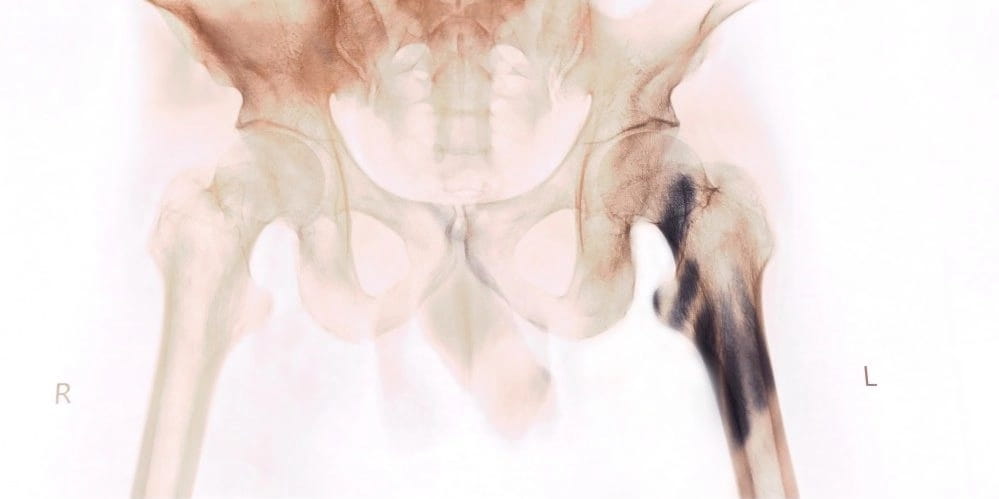

3. Смещение позвонков

Ноющая боль в крестце возникает из-за смещения позвонков. Данный недуг в медицине называют спондилолистезом. Несвоевременное обращение за медицинской помощью грозит серьезными последствиями, вплоть до инвалидности.

Смещение позвонков можно разделить на четыре стадии развития, каждый из которых имеет свою симптоматику.

Начальная стадия не обладает выраженными признаками, но они имеют место быть. Крестец болит при наклонах или резких движениях, после поднятия тяжелых предметов или длительных физических нагрузок.

На второй стадии боли в крестце становятся частыми и продолжительными, особенно после активных движений.

На третьей стадии истощаются межпозвоночные диски, и проседает позвоночный столб. Боли крестца становятся сильными и приступообразными, сковываются движения, что доставляет весомый дискомфорт.

Четвертая, заключающая, стадия – переход недуга в хроническую форму, которая проявляется: